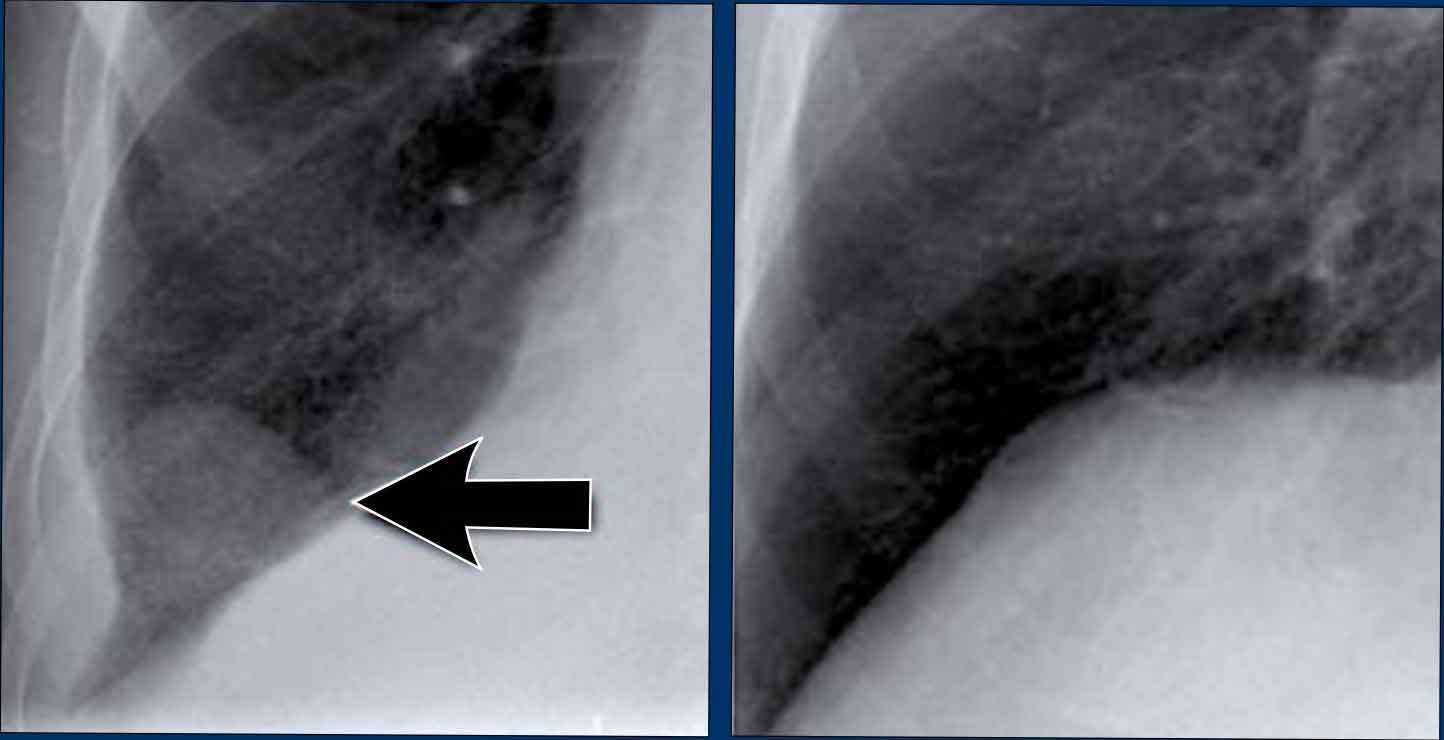

Pectus excavatum

In patients with pectus excavatum, the right heart border may appear indistinct on frontal chest radiographs.

This appearance can mimic right middle lobe consolidation or atelectasis due to loss of the normal silhouette (silhouette sign).

lateral chest radiograph is particularly useful in such cases to confirm the diagnosis.

Pectus excavatum is a congenital anterior chest wall deformity characterized by posterior displacement of the sternum and adjacent costal cartilages, resulting in a concave appearance of the anterior thoracic wall.